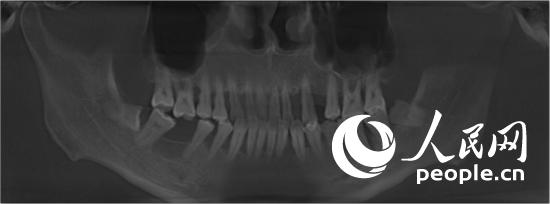

牙周炎患者的口腔內部照片和x光片(人民網(wǎng)記者張希 攝)

李醫(yī)生從她的眾多牙周病例里調出一位患者的口腔內部照片和x光片說:“這是一個牙周炎病例,病人很年輕(1982年生),來看的時候幾乎全口牙齒都松動,有些已經(jīng)被拔除。在這個x光片中,牙根周圍呈黑色陰影的部分,意味著牙槽骨已經(jīng)被破壞。由于牙周炎導致牙槽骨被破壞,牙齒就會慢慢出現(xiàn)松動、移位、甚至脫落。同時,牙槽骨被破壞后,牙齦也會跟著萎縮,導致牙縫變大!崩钺t(yī)生還表示,牙周炎最具破壞性的一點就在于,其對牙槽骨的破壞是不可逆的。上述病例就屬于重度牙周炎患者,從他的口內照片中可以看到出血、流膿、牙齒移位、牙縫變大等情況;從其全口X光片中可以看出,牙齒周圍骨頭已遭到嚴重破壞。